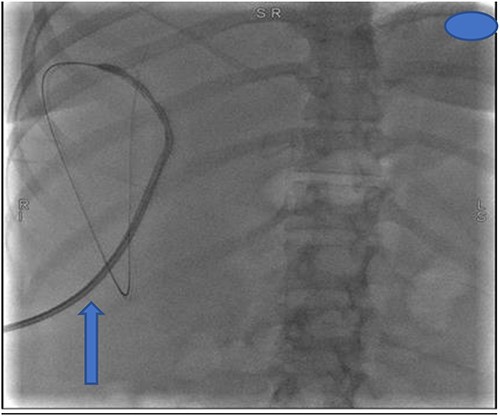

At our facility, ERCP was done. The bile duct was cannulated with 0.035 wire-guided sphincterotome. Cholangiogram showed normal caliber biliary tree with one filling defect in the distal CBD and contrast leak from duct of Luschka to the gall bladder bed (Fig. 1). There was no contrast leak from the cystic duct stump (Fig. 2A). Standard sphincterotomy was performed and a single mulberry stone was removed using stone retreival balloon and double pig tail biliary plastic stent was placed into the RHD and good bile flow was achieved post procedure (Fig. 2B).

Fluoroscopy image indicating bile leak from type 2 duct of Luschka.

(A) First fluoroscopic image shows evidence of no bile leak from cystic duct stump as indicated by the arrows; (B) second fluoroscopic image shows a stent placed into the RHD.